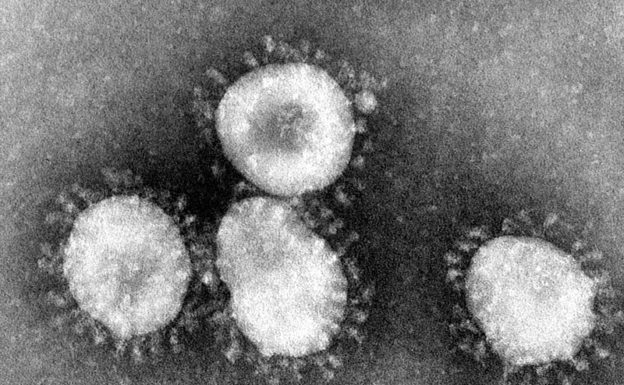

中央流行疫情指揮中心今晚宣布,一名台灣女性返台時主動通報並確診武漢肺炎,直接就醫未進入社區,同機乘客等 46 名接觸者在追蹤中。疾管署提升武漢旅遊建議到第三級警告,民眾非必要別去。

中國傳染病權威鍾南山在 21 日出席廣東省政府記者會時指出,武漢新冠狀病毒如果出現二代人傳人現象,疫情將會很快擴散,尤其必須密切注意超級傳播者,避免第三波爆發。

德國權威病毒學者德羅斯登 22 日表示,照目前跡象來看,武漢肺炎的疫情不會比 SARS 嚴重,他相信中國政府有能力阻止這種新型病毒的傳播。

新型冠狀病毒引起的肺炎從中國武漢往外擴散,中國疾病預防控制中心主任高福今天表示,病毒的來源很可能是市場銷售的野生動物,而病毒在逐漸適應,可能變異,往外進一步擴散。